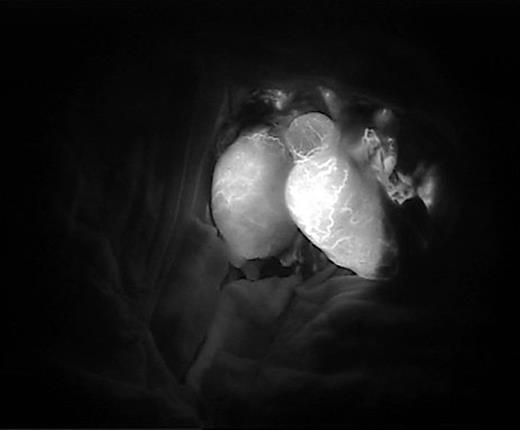

Cooperative surgery was performed by surgeons from the urology and plastic surgery departments. The patient was placed supine in a frog-leg position. The proximal gonadal artery in the spermatic cord was detected easily with pulsating bleeding and secured by clamping without causing vessel injury (Fig. 2). The vas deferens was also found near the gonadal artery with a resilient tactile sense. Thin lumens around the gonadal artery were identified as gonadal veins. The amputated testis was also checked, and the vas deferens was continued from the tail of the epididymis. The gonadal artery was located in the same direction as the vas deferens. The testis was fixed on the scrotal wall to prevent it from roaming freely. The gonadal artery was first connected using 11-0 nylon under an operating microscope (KINEVO 900, Zeiss; Fig. 3). After vein drainage was confirmed, gonadal vein anastomosis was performed with 11-0 nylon (Fig. 3). Lastly, two-layer vasovasostomy was carried out with 8-0 nylon (Fig. 3). After the end-to-end anastomosis of the artery, vein, and vas deferens, the viability of the testis could be confirmed in terms of vascularity on gross and indocyanine green fluorescence perfusion (Fig. 4). The cremasteric muscle of the spermatic cord was reinforced to reduce tension in the anastomosis sites, and orchiopexy was performed to prevent testicular torsion. The other testis was replanted in the same maneuver (right testis: artery 1ea, vein 1ea; left testis: artery 1ea, vein 2ea). The ischemic time of each testis was 7 h (right) and 8.5 h (left). Each testis was raised on a high scrotal area and fixed with the approximated dartos fascia because of the large skin defect of the scrotum (Fig. 5). Lastly, the amputated scrotal wall after defatting was used to cover the whole defect.

We performed five examinations to check the viability of the replanted testis. First, in the operating room, we used indocyanine green after replantation (Fig. 4). Indocyanine green fluorescence perfusion showed testicular perfusion, which enabled the immediate checking of the viability of vessels. This procedure is appropriate for checking the viability of microscopic vessels that may be damaged during a milking test. Second, a testicular scan showed the viability of the testis (Fig. 7). One testis is markedly different from the lesion of orchiectomy. However, the scan resolution was low because of a wide range of arterial courses and the disturbance of the urethral catheter or bladder. Third, contrast-enhanced CT displayed the vascularity of the testis and the surrounding parts (Fig. 8). However, the shooting time to the enhanced phase could affect the failure of the vascularity of the testis. No protocol for this case has been established in our institute; therefore, CT was a nonspecific tool for testicular examination. Fourth, ultrasonography efficiently showed the vascularity inside the testis (Fig. 9). However, skin wound could inhibit or limit ultrasonography. Fifth, we indirectly checked the testicular function based on testosterone levels (Fig. 10). A laboratory examination should be performed continuously. However, this procedure could be limited among hypogonadal men, and the separate testicular function of each testis could not be easily identified. Nevertheless, these techniques will help determine the viability of the testis in specific situations.